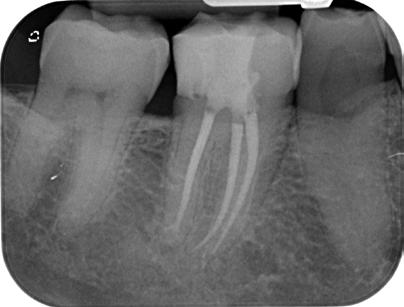

20. ábra: Posztoperatív röntgenfelvétel.

21. ábra: Kiindulási felvétel. Az elhalt felső nagyőrlőfog rágás során panaszokat okoz a páciens számára. A felvételen jól látható a gyökércsatorna-rendszer beszűkültsége.

33. ábra: Posztoperatív felvétel.

26. ábra: Posztoperatív röntgen.

jelent az endodonciai kezelések során, de a cikkben említett három gyakorlati tapasztalaton alapuló szabály követésével ki tudjuk használni az anatómiai jellegzetességekből fakadó előnyöket, valamint olyan célszerszámokat tudunk alkalmazni a trepanációs nyílás kialakítására és a gyökércsatorna-bemenetek lokalizálására, amelyek sokkal biztonságosabbá és kiszámíthatóbbá teszik az egész folyamatot. Ezáltal csökken az álutak és perforációk kialakulásának valószínűsége. Apróbb változtatásokkal és ha következetesen ugyanazon protokoll szerint végezzük beavatkozásainkat, hosszú távon sokkal sikeresebbek lehetünk. Ez a cikk eredetileg a Dental Tribune France 16. kötetének 2024/5. számában jelent meg.